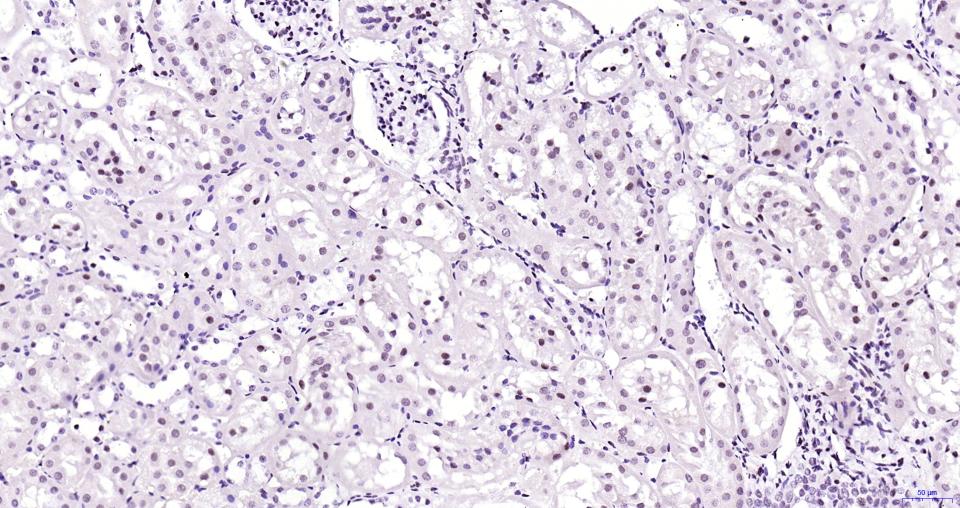

Paraformaldehyde-fixed, paraffin embedded Human Kidney; Antigen retrieval by boiling in sodium citrate buffer (pH6.0) for 15 min; Antibody incubation with BRD4 Monoclonal Antibody, Unconjugated(bsm-61190R) at 1:200 overnight at 4°C, followed by conjugation to the bs-0295G-HRP and DAB (C-0010) staining.